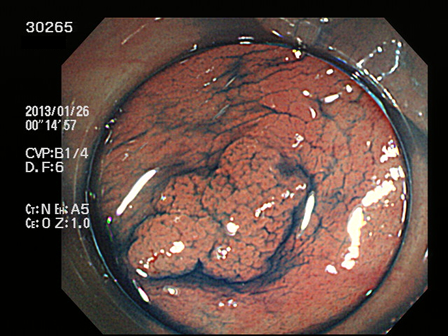

上記100名より抽出した平坦・陥凹型腺腫(=癌化の危険が高いが見落としやすい病変)の内視鏡写真